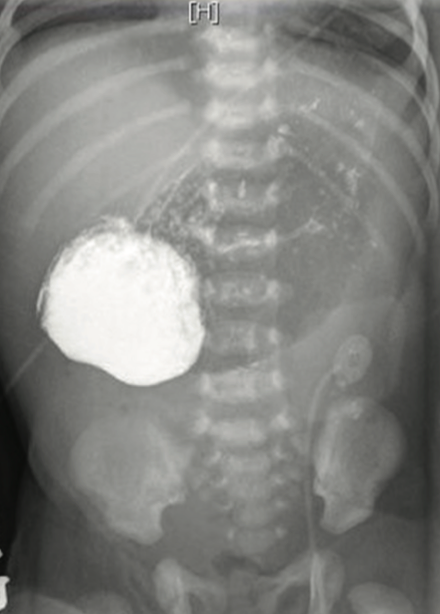

Anshu Kumari, MD; Magda Mendez, MD, FAAP; Sandra Camacho, MD; Amir Navaei, MD

Echogenic bowel has been defined as bowel of similar or greater echogenicity on ultrasonography than surrounding tissues, such as liver, bones, and lung.